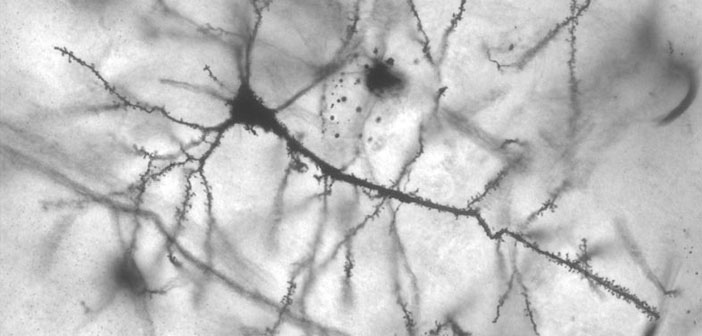

Galime pasidžiaugti, kad Lietuvoje dirbančių gydytojų – epileptologų atlikti tyrimai ir rašomi straipsniai pristatomi tarptautiniuose leidiniuose. Straipsinis apie tai, kaip asmenys dirbantys su sergančiaisiais epilepsiją, ligą supranta jų piešiniais. Už pasidalintu straipsniu dėkojame prof. dr. R.Mameniškienei. Painting-LASSE-2019 Skaityti daugiau